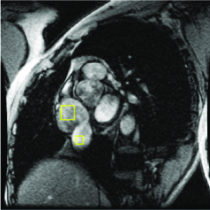

Appearance is one of the most important visual cues to distinguish between different structures in an image. Appearance is described by studying the distribution of different features such as intensity values in gray-scale images, color, and texture inside each object. In most cases, appearance models are incorporated into the data term in (2) and (7). The purpose of incorporating appearance prior is to fit the appearance distribution of the segmented objects to the distribution of objects of interest, e.g. using Gaussian mixture model (GMM) (Rother et al., 2004). In the literature, there are two ways to model the appearance: 1) adaptively learning the appearance during the segmentation procedure, and 2) knowing the appearance model prior to performing segmentation (e.g. by observing the appearance distribution of the training data). In the former case, the appearance model is learned as the segmentation is performed (Vese and Chan, 2002) (computed online). In the second case, it is assumed that the probability of each pixel belonging to particular label is known, i.e. if represents a particular set of feature values (e.g. intensity/color) associated with each image location for object, then it is assumed that is known (or pre-computed offline). This probability is usually learned and estimated from the distribution of features inside small samples of each object. Figure 9 illustrates the probability of different structures (the kidney, the tumour, and the background) in an endoscopic scene. A lower intensity in Figures 9(b-d) corresponds to higher probability.

More advanced texture features such as those based on Haar and Gabor filter banks have shown many successes in medical image segmentation (Huang et al., 2005; Malcolm et al., 2007; Santner et al., 2009). Koss et al. (1999) and Frangi et al. (1998) are two works that utilized advanced features to segment abdominal organs and to measure vesselness, respectively. In (Frangi et al., 1998), the eigenvalues of the image Hessian matrix are used for measuring the vesselness of pixels in images. This measure is used for liver vessel segmentation both in a variational framework (Freiman et al., 2009) and in a graph-based framework (Esneault et al., 2010). Statistical overlap prior is another strong appearance prior that has been proposed by Ayed et al. (2009). Their method embeds statistical information (e.g. histogram of intensities) about the overlap between the distributions within the object and the background in a variational image segmentation framework. They used the Bhattacharyya coefficient measuring the amount of overlap between two distributions, i.e. if . Ben Ayed et al. (2009) used this strong prior to segment left ventricle in MR images.